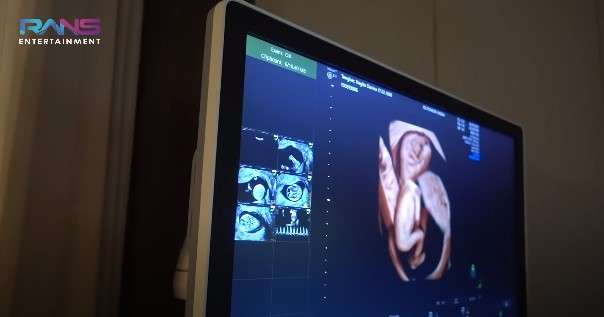

Dalam tayangan di kanal YouTube Rans Entertainment, Nagita Slavina membagikan momen saat dirinya melakukan cek USG 4D. Dengan teknologi tersebut, Gigi bisa melihat perkembangan janinnya lebih jelas.

Calon adik Rafathar itu terlihat aktif dalam pemeriksaan dokter. Sempat khawatir dengan keadaan calon anak keduanya, Gigi pun sekaligus berkonsultasi dengan dokter yang menangani.

Meskipun kondisi tersebut masih wajar, namun dokter menyarankan kepada Gigi untuk memperbanyak istirahat di tengah kesibukannya. (YouTube/Rans Entertainment)